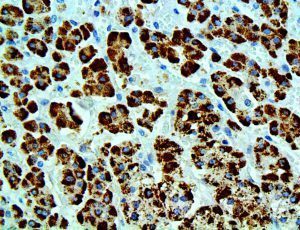

The first cytokines released are interleukin 1β (IL-1β) and tumor necrosis factor-α (TNF-α), which attract a variety of circulating white blood cells (WBCs) to the infection site, including neutrophils, monocytes, macrophages, and natural killer (NK) cells. This response, along with the antipathogenic chemicals released by these cells (i.e., complement), comprise the innate immune response. These cells directly attack the invading pathogen and also release additional cytokines, chief among them interleukin-1 and 6 (IL-6). IL-6 is essential for invoking the adaptive immune response, which calls T-cells, B-cells, and T helper (Th) cells to the infection site. IL-6 also stimulates further recruitment, proliferation and activation of macrophages.

This activation induces inflammatory monocytes to highly express IL-6, starting a localized and then systemic cascade effect that results in hyperproduction of IL-6, which accelerates the inflammatory process. Because IL-6 also increases vascular permeability, excessive levels cause blood vessels to become very leaky. This, along with clotting factors released from vascular endothelial cells, stimulates the coagulation cascade, resulting in microthrombosis (tiny clots), which leads to ischemia and tissue death of the kidney, intestines, heart, liver, brain and extremities.